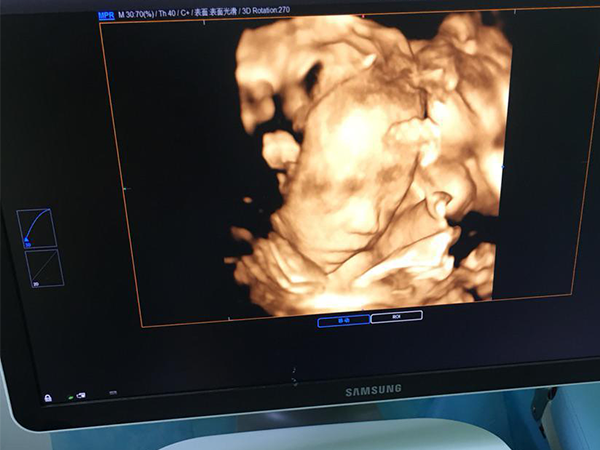

四维彩超的图片暗藏玄机,这些看生儿子的小技巧一定要get到

孕妇在怀孕24周后,胎儿各项身体结构已基本生成,这时需要通过彩超来进行排畸检查。四维彩超排畸检查是能清楚的看到胎儿的各项身体发育状况的,因此也能通过四维彩超辨别胎..